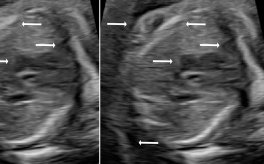

Three in vivo Bmode fetal images with and without aberration correction are presented in Figs. 10-12. GIF images of examples A-L (see Fig. 9 and Table 5) alternating between the corrected and uncorrected images are uploaded as supplementary material. The differences in image quality are easier to appreciate in the GIFs than in a side-by-side comparison. The data points for the three examples are colored black in Fig. 9. Table 5 give tabular values for the global sound speed estimate, sharpness increase (κ𝜅\kappa) and answers from the clinical evaluations.

The in vivo examples A-C, in Figs. 10-12 respectively, show different nuances of how sound speed aberration correction improves focusing quality. A noticeable improvement in Fig. 10 is the improved contrast and clarity of borders. The sound speed correction seems to remove the double structure indicated by the arrows in Figs. 10c-10d. The skull border and the brain structures in Fig. 11 are also better defined and clearer after aberration correction. Example C in Fig. 12 is the image with the highest increase in Tenengrad κ𝜅\kappa, seen from Fig. 9 and Table 5. The improvement in image quality is evident around the boundary of the fetus body and the correction sharpens the structures indicated by the arrows. The improved contrast between the layers in the shallow tissue layers is also noticeable.

Example J, found in the supplementary material, shows images of a fetal head for which the three evaluators preferred the 1540 m/stimes1540dividemetersecond1540\text{\,}\mathrm{m}\text{/}\mathrm{s} image. The sound speed correction seems to sharpen the skull and tissue outside the head, but seems to defocus the structures on the left-hand side of center inside the head. A potential fix for this case is to use a smaller kernel size for smoothing the sound speed map, enabling more rapid spatial variations in average sound speed. Example G shows similar mixed corrections, and the corrected image was preferred by one clinician and the uncorrected preferred by two.